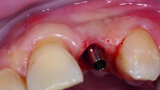

Digitising your implant practice